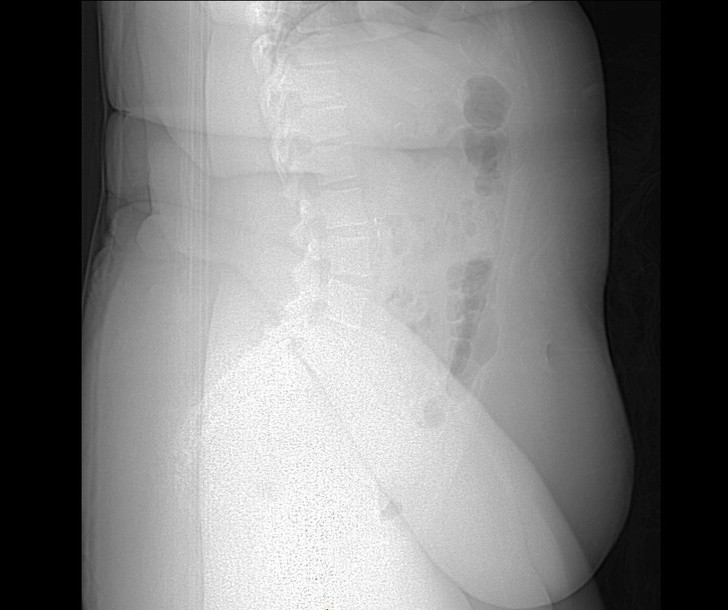

9. Prześwietlenie osoby cierpiącej na otyłość. Nadmierna tkanka tłuszczowa utrudnia zobaczenie znajdujących się pod nią kości

9. Prześwietlenie osoby cierpiącej na otyłość. Nadmierna tkanka tłuszczowa utrudnia zobaczenie znajdujących się pod nią kości © Living Art Enterprises/EAST NEWS